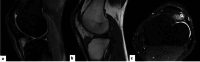

The authors present a case of fibroma of the tendon sheath with intra-articular location in the knee, more specifically in the infrapatellar fat; with this specific location, this is the fourth case described of an entity that rarely affects large joints. Clinical and epidemiological aspects, but especially the imaging findings on magnetic resonance imaging scans, are essential for the differential and definitive diagnosis, which was nevertheless established only after a histological study of the excised mass by miniarthrotomy.